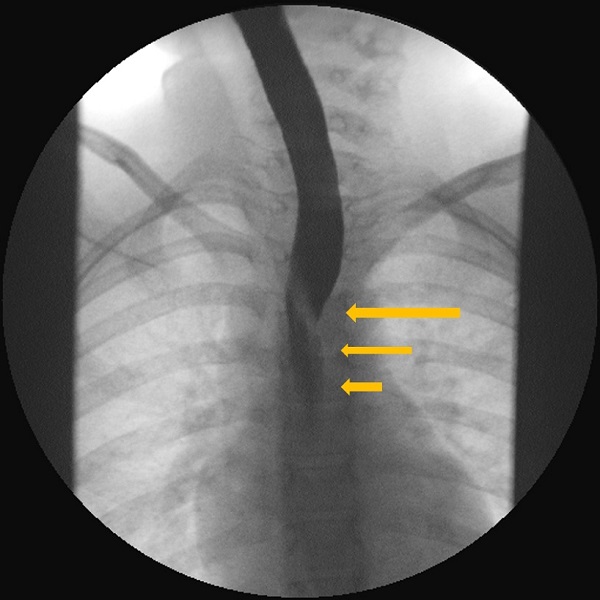

La exploración física es normal, con adecuado desarrollo ponderoestatural. Se realiza un estudio esófago-gastroduodenal con contraste baritado, en el que se pone de manifiesto una impronta sobre la pared posterior de la porción torácica del esófago, en relación con diagnóstico ya conocido de arteria subclavia derecha aberrante (Figs. 1, 2 y 3).

| Figura 1. Estudio esófago-gastroduodenal con contraste baritado. Proyección anteroposterior. Se observa la impronta oblicua de la arteria subclavia derecha aberrante (ARSA) en el tercio medio esofágico |

|---|

![]() |